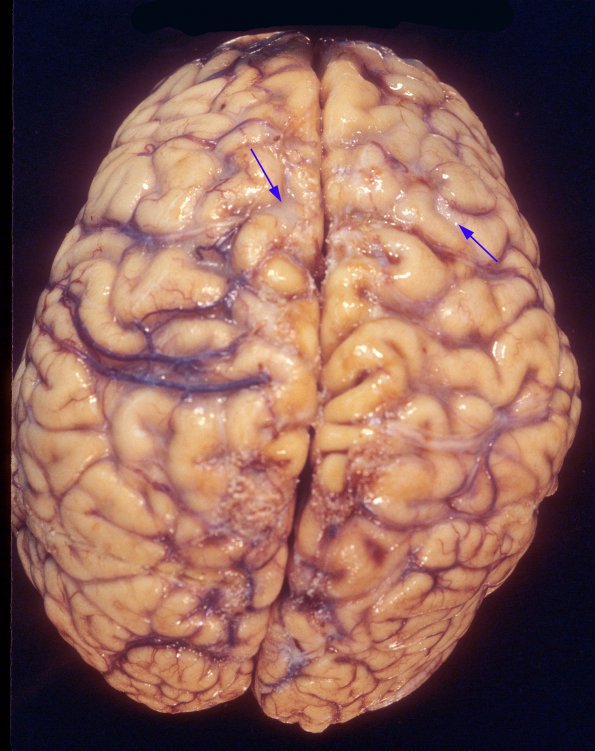

Gross neuropathology of histoplasma leptomeningitis shows accumulated infiltrate in the subarachnoid space (arrows)